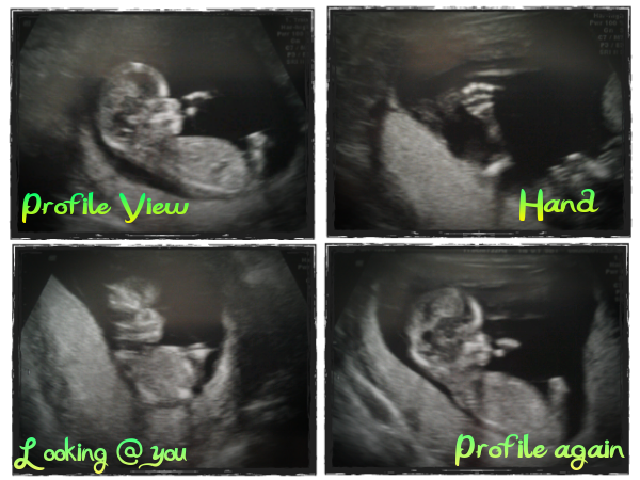

So, onto my NT scan. Apart from literally having to wait an hour and a half, it went really well! Apparently if whatever they're measuring in the back of the baby's neck is wider than 3mm it causes concern; our little Sea Monkey's neck thingy was barely over 1mm. So that along with blood tests I got at my last OB appointment means we have screened negative for a handful of chromosomal abnormalities. This does not mean it is impossible, but its just a lot less likely. Add that to the whole "healthy 23 year old" thing and I don't feel the need to do any further (and much more invasive) procedures.

The ultrasound itself was amazing, too. Since this office has a much stronger machine, everything was so clear. The Sea Monkey didn't put on that much of a performance, (s)he did have a few hicups, which was flipping adorable. (S)he also kept bringing their hand up to their face (quite quickly) so in the pictures it looks like they're sucking their thumb.

The ultrasound person tried to figure out the sex of the Sea Monkey, but from one angle it looked like a boy, from another it looked like a girl. She tried to get the little sucker to roll over but apparently my Sea Monkey didn't want to...I almost asked if it would help if I did a handstand or something, but I thought that would be weird, lol. Instead I just called my baby a jerk for the first time (hahaha) and accepted the fact I'd have to wait to find out what we're having.

PS - the ultrasound picture where the Sea Monkey is looking straight at you is totally creepy looking...but it doesn't compare to the 3D picture they took - which I'm not sharing with you cuz it'll probably give you nightmares. Seriously people, 3D Ultrasounds should not be performed at merely 12 weeks, because the baby is still waaaaay too alien-esque.